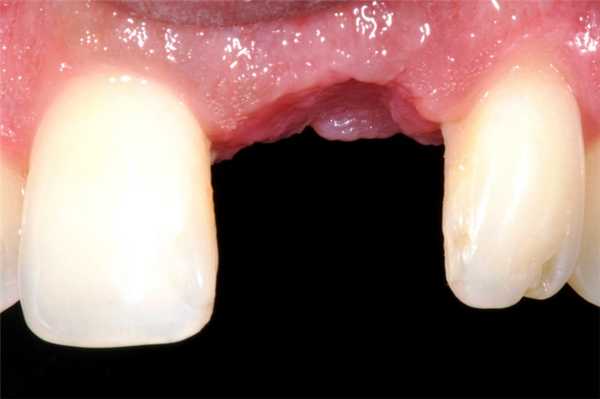

Перелом коронки или корня удаляемого зуба - самое частое из всех местных осложнений. В ряде случаев оно связано со значительным поражением зуба кариозным процессом, иногда зависит от анатомических особенностей строения корня и окружающей костной ткани (длинные, тонкие или сильно изогнутые корни при толстых межкорневых перегородках и неподатливых стенках лунки, неравномерное утолщение или значительное расхождение корней). Довольно часто это осложнение возникает вследствие нарушения техники операции: неправильного наложения щипцов, недостаточно глубокого их продвигания, резких движений во время вывихивания зуба, грубого и неправильного применения элеватора и т. д.

В случае перелома корня зуба необходимо продолжить вмешательство и удалить его. Оставление отломанной части корня, как правило, приводит к развитию воспалительного процесса в окружающих тканях. Повторная операция в этом случае проводится через 7-10 дней, к этому сроку воспалительные явления обычно стихают.

Осложнения, связанные с костными структурами

Чаще всего во время удаления случается перелом корня зуба. В этом случае его обычно удаляют, чтобы не спровоцировать воспалительный процесс. Если же симптомы заражения уже возникли, а патология обнаружилась через несколько дней после операции, ждут 1-1,5 недели и проводят хирургическое лечение повторно. При этом пациент принимает противовоспалительные препараты, чтобы остановить процесс воспаления.